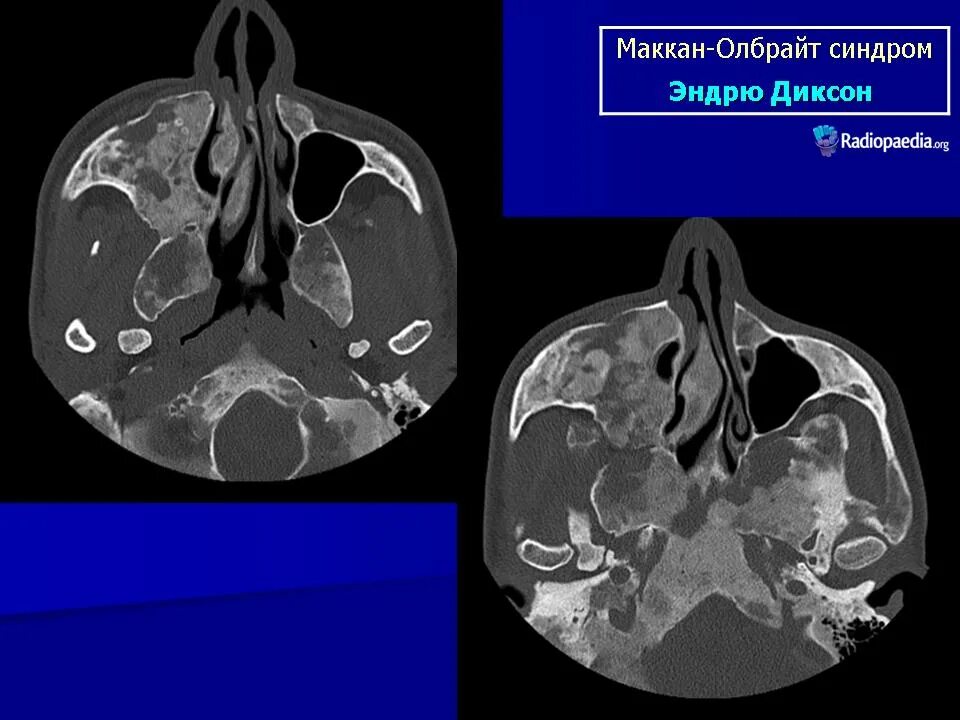

Синдром олбрайта